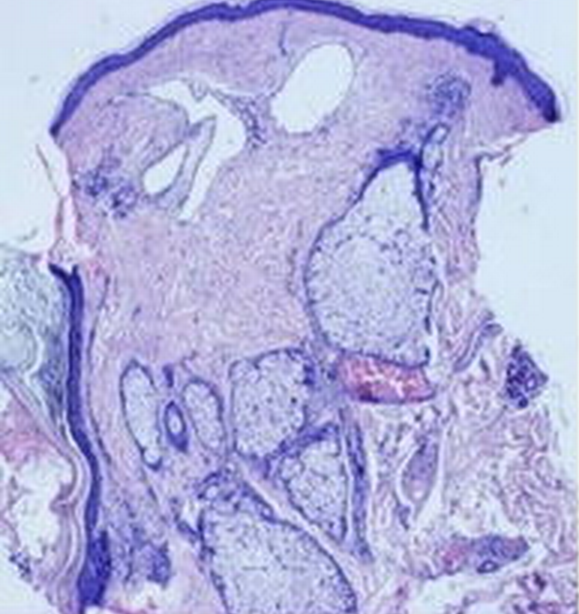

鮮紅斑痣病理